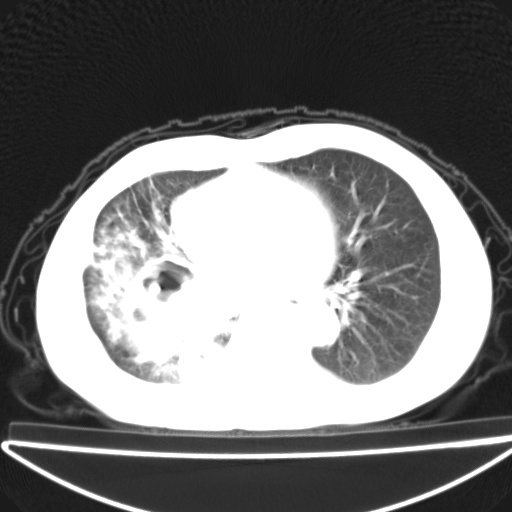

以下是引用jsgdoctor在2008-11-6 22:12:00的发言:[br]右主支气管壁明显增厚,管腔狭窄.考虑为右侧中央型肺癌伴阻塞性炎症\\肺脓肿.

以下是引用zjzjr在2008-11-6 20:25:00的发言:[br]中心型肺ca,合并阻塞性肺炎

以下是引用zsl6918在2008-11-6 19:43:00的发言:[br]右侧中心性肺癌(鳞癌)